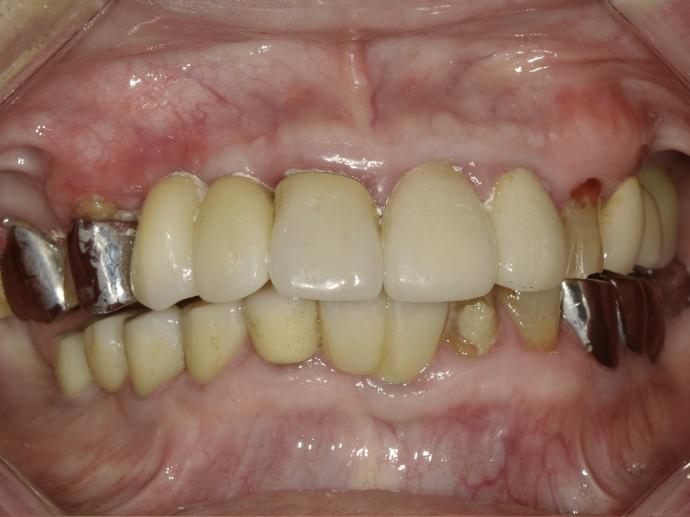

術前 / 術後

年屆八十的曾先生住竹山,為人幽默風趣。之前長年佩戴的活動假牙總覺得不甚方便。曾先生說,「老蒙老,還要哺土豆」,希望能夠用植牙取代活動假牙。一面不必再拿上拿下清洗,一面能咬較硬的食物,充分享受美食帶來的樂趣。

曾先生血壓較高,但在安馨溫馨的手術室中,以醫療級血壓血氧儀全程監控,將血壓監控在安全的範圍內。幾次手術下來,完成八顆的植牙,也達成他能享受美食的心願。